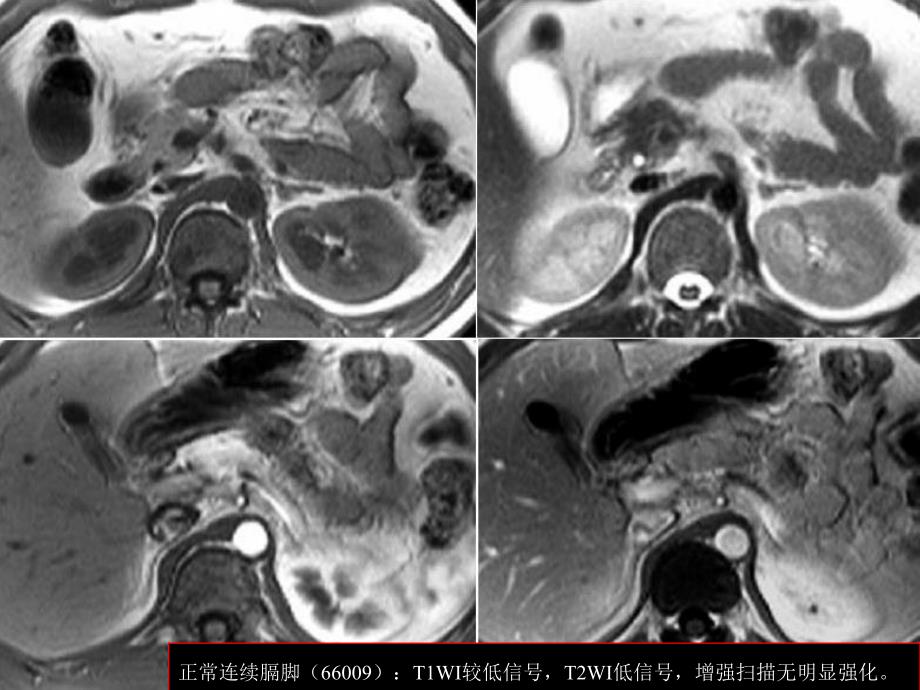

正常连续膈脚(159719,F46)正常连续膈脚(66009):T1WI较低信号,T2WI低信号,增强扫描无明显强化。膈脚不均匀肥厚(202300,M57):平扫密度比血管高,增强扫描呈缓慢轻度强化。膈脚不连续(189701,M41)多结节膈脚(158229)膈脚(80875,M32):结节状膈脚易误为肿大淋巴结。膈脚(183833,M40):误为肾上腺增生。膈脚(186619,F80):结节状膈脚易误为肿大淋巴结。膈脚(205030,M45):结节状膈脚易误为肿大淋巴结。膈脚(186939,M60):同一次检查,不同呼吸状态扫描,膈脚形态不同。膈脚(205540,F70):同一次检查,不同呼吸状态扫描,膈脚形态不同。膈脚分叉(204845,M65)